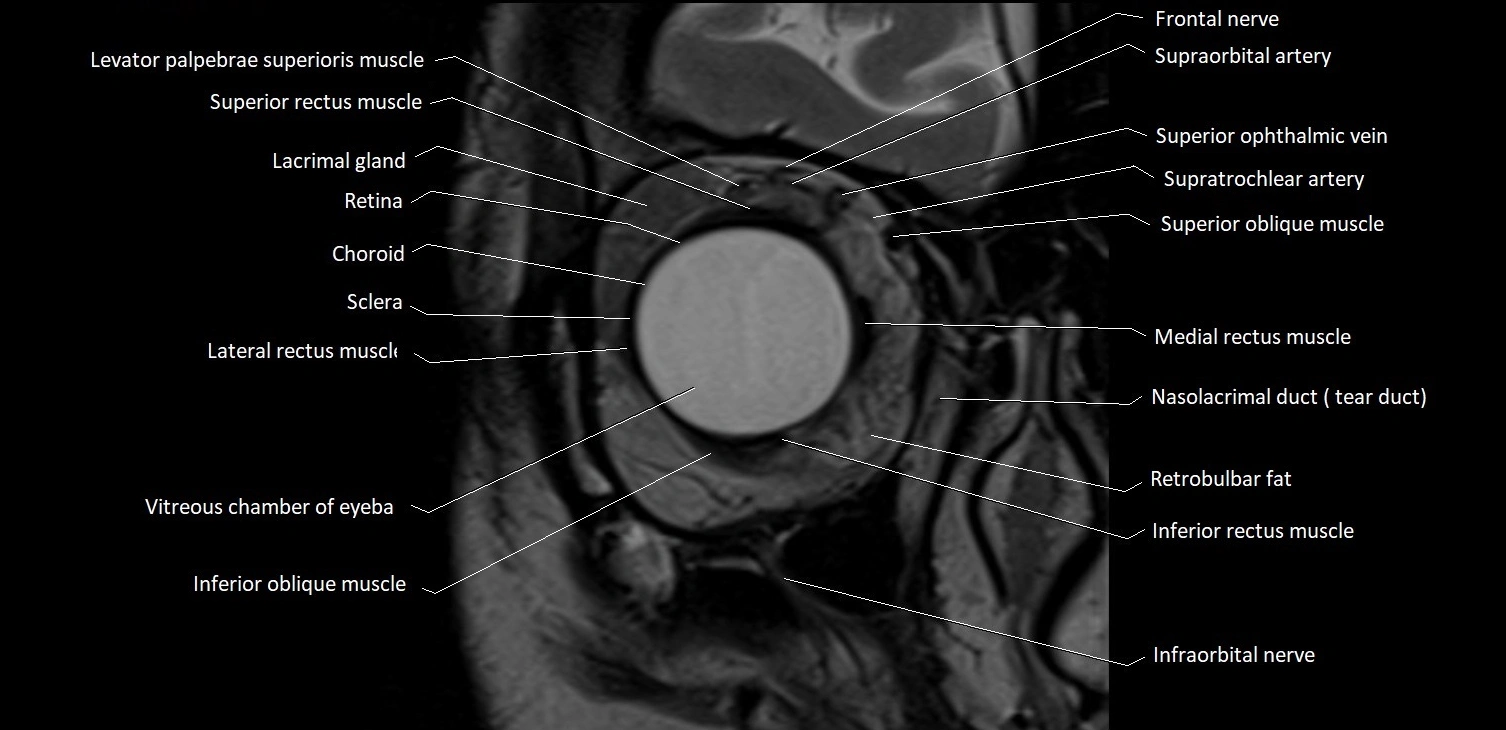

MRI images